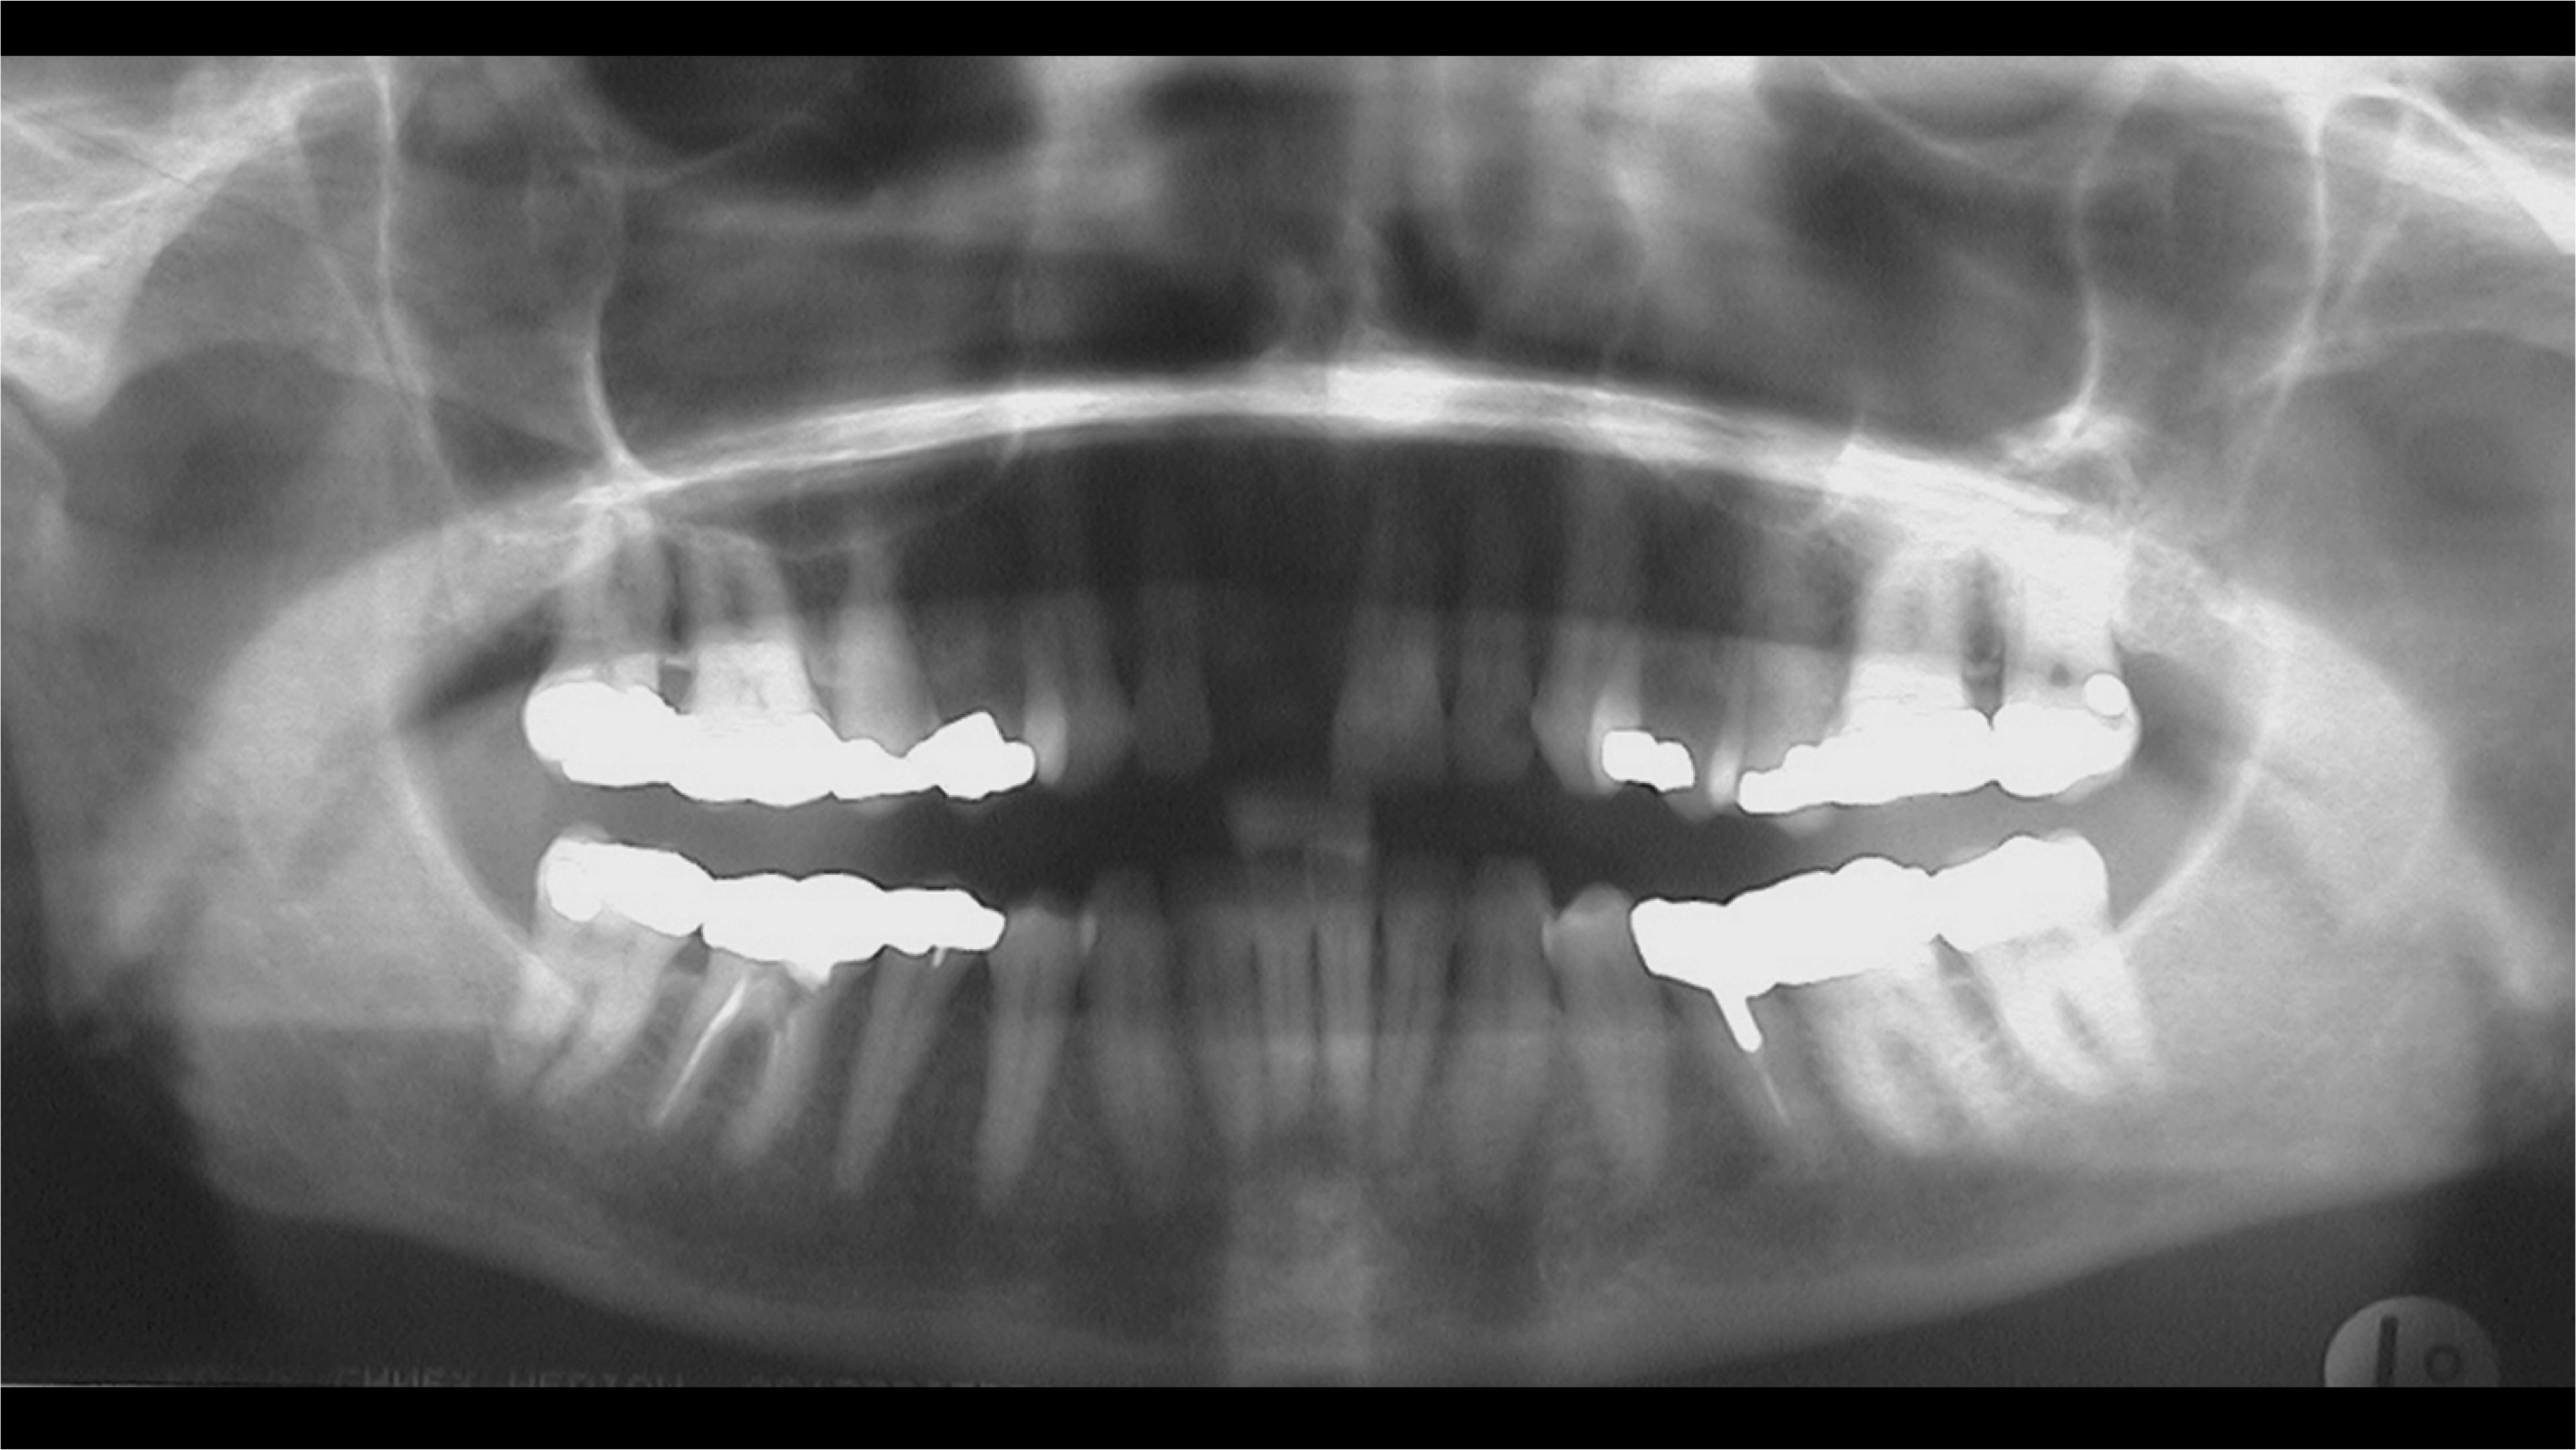

Radiographic examination of the site for implant placement is essential to determine the presence of adequate space for the implant and subsequent restoration (eg, central incisor) and to assess soft-tissue architecture.1,2 Computed tomography (CT) images and panoramic radiographs (eg, panorex) have been used in implant dentistry to help identify structures critical for implant placement and establish the safe, short distance for implant placement (ie, vertical control of implant placement) using a pilot drill (Figure 4).5

Pilot drills, which are typically 2 mm wide, are used to drill into the trajectory of the bone to a short, safe distance to establish position and angulation (Figure 7). Care must be taken to observe the premaxilla angulation, which averages 20 degrees. Then, a direction-indicating pin is placed (Figure 8) and a radiographic image is taken (Figure 9).7 This image (eg, panorex) is enlarged to enable further analysis and measurements, particularly to establish the exact height of bone.

The approximate 20% horizontal and vertical distortion is calculated.4 This can be accomplished by measuring from the top of the guide pin to the opposing vital structure (eg, floor of the nose, 5 mm). Because of the 20% distortion, the actual measurement is 4 mm. Thus, there is a total of 14 mm of vertical bone height (ie, 10 mm for the length of the pin, plus 4 mm to the floor of the nose), and a 13-mm-length implant would be selected.

Fig 4. Radiographic imaging was used to establish vertical control of implant placement and ensure the presence of sufficient bone on either side of the implant.

Figure 4

Fig 9. An enlarged panorex image with the direction-indicating pin in place was used to plan proper implant placement depth, particularly in the context of the exact height of bone.

Figure 9